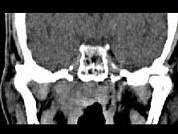

男,52岁,血涕3月余。CT如图所示,最可能的诊断为 ( )A、小唾液腺瘤B、咽旁脓肿C、咽旁混合瘤D、咽部神经纤维瘤E、鼻咽癌

问题 男,52岁,血涕3月余。CT如图所示,最可能的诊断为 ( )

选项 A、小唾液腺瘤 B、咽旁脓肿 C、咽旁混合瘤 D、咽部神经纤维瘤 E、鼻咽癌

答案 E